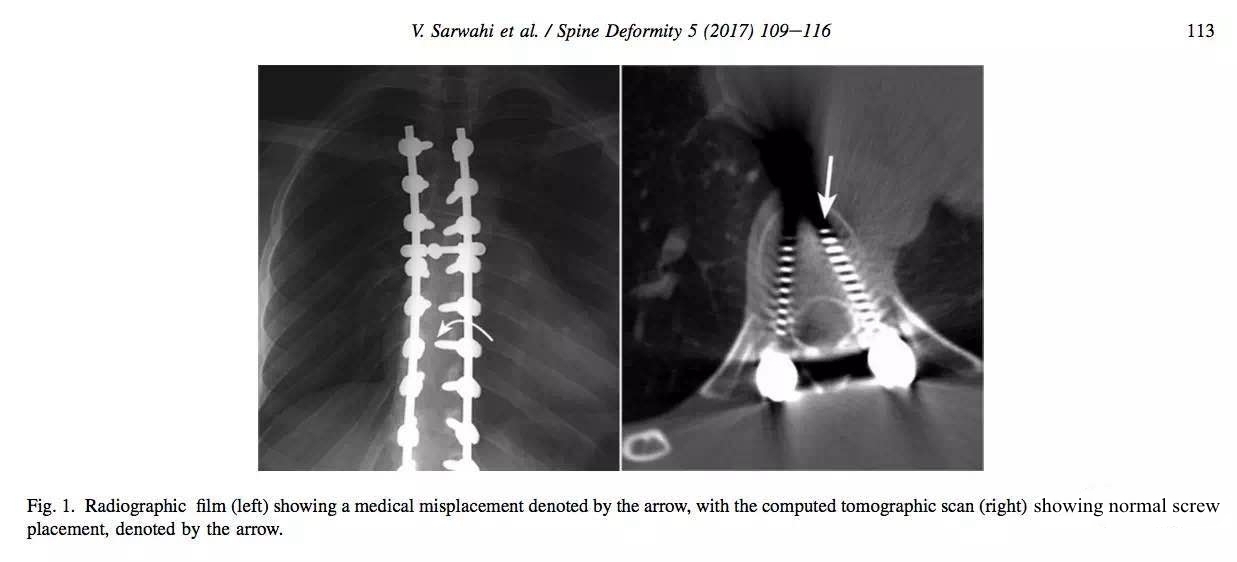

X线片显示钉尖超过棘突,钉道可能偏内进了椎管。但CT复查显示位置良好。